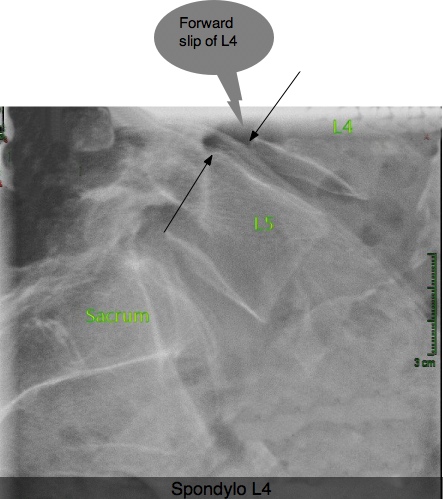

Spondylolysthesis most authorities now seem to agree is a fracture in

the spine, usually occurring in early childhood, allowing one vertebra to

slide forwards on another. Mostly it causes nagging low back pain and

sometimes tingling in feet and legs. Very occasionally it is a serious

problem... and sometimes in the older patient it is caused by wear and tear of the facet

joints in the spine.

SPONDYLOLYSTHESIS ...